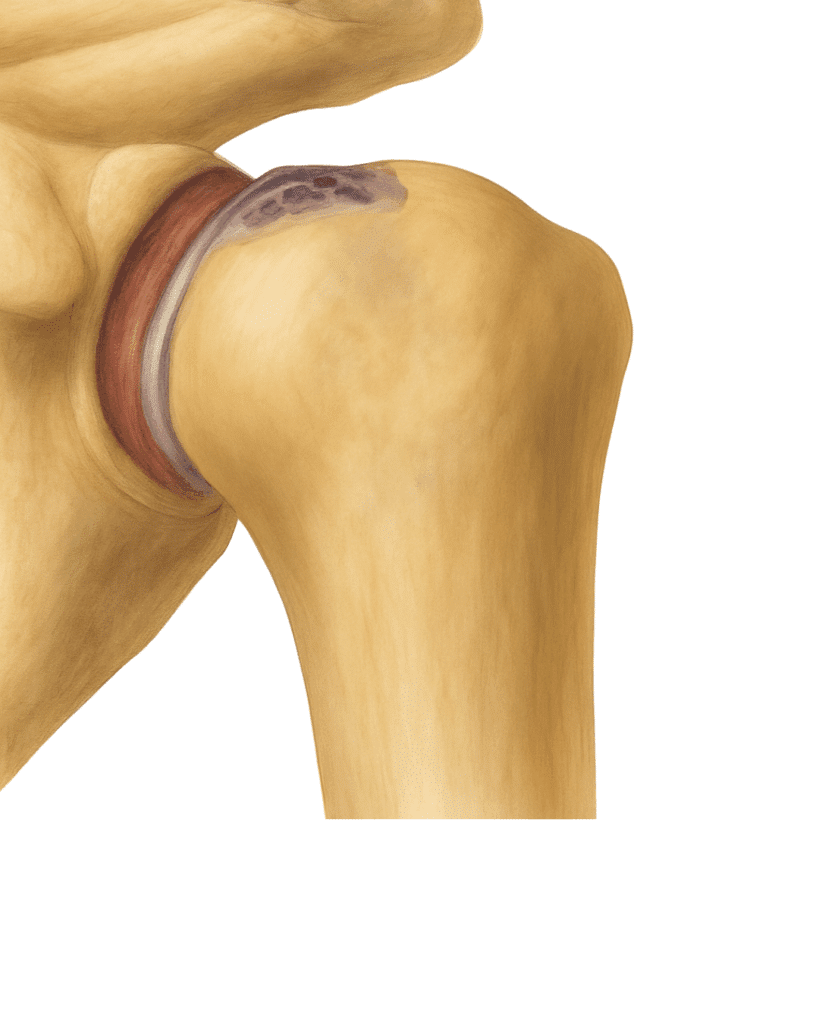

Other conditions can also harm the joint. A severe fracture can shatter the ball of the shoulder (humeral head). Avascular necrosis occurs when the bone loses its blood supply, which can cause the bone to die and collapse.

The shoulder is a ball-and-socket joint. The rounded top of your upper arm bone (the humeral head) fits into a shallow cup on your shoulder blade (the glenoid). This design allows a wide range of motion for lifting, reaching, and rotating.

Cartilage, a smooth, rubbery layer, covers the ball and lines the socket, letting the joint glide without friction. The rotator cuff—a group of four muscles and their tendons—keeps the joint stable and powers your arm movements.

When the Shoulder is Damaged

With osteoarthritis, cartilage cracks and thins, causing bone surfaces to become rough. This can lead to bone spurs, grinding, and stiffness. Inflammatory arthritis can make the joint warm, swollen, and painful. A large rotator cuff tear can allow the joint to slip out of position, damaging cartilage and causing persistent pain. In cases of avascular necrosis, the lack of blood flow leads to bone collapse.

Osteoarthritis is joint wear and tear. Cartilage cracks and thins, and bone rubs on bone. This leads to roughened bone and growths called bone spurs. The joint is stiff and painful. It may catch when it moves.

A large rotator cuff tear lets the joint slip out of place. This can lead to cartilage damage and weakness and pain in the joint.